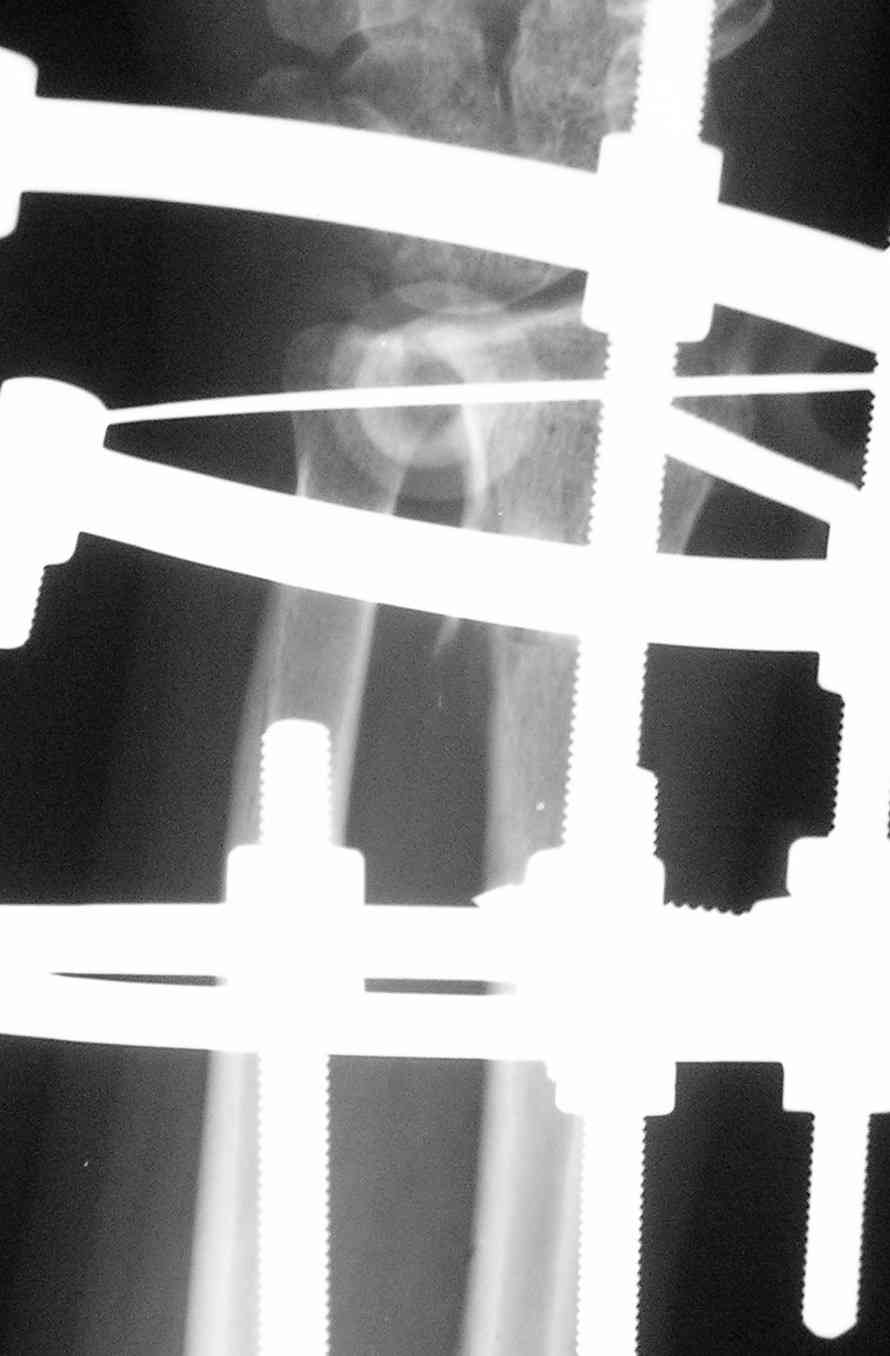

Спице-стержневой аппарат с компактотомией лучевой кости, костная пластика локтевой с удалением пластины. Не комфортно, но больше шансов на благоприятный исход. Заканчиваю лечение с похожей деформацией лучевой кости.

Виктор.

Виктор, спасибо за высланные фото и Ргграммы.

У больного/ой кроме перелома лучевой кости и шиловидного отростка локтевой, разрыв дистального радиоульнарного сочленения, перелом ладьевидной кости и ладьевидно-полулунная диссоциация.

Если позволите свое мнение, не стал бы лечить аппаратом эту травму, перелом луча не консолидировался: открытая репозиция+ костная пластика+ пластина, синтез ладьевидной кости, по возможности шов ладьевидно полулунной связки,

если восстановить связку не представляется возможным, фиксация 2 спицами.